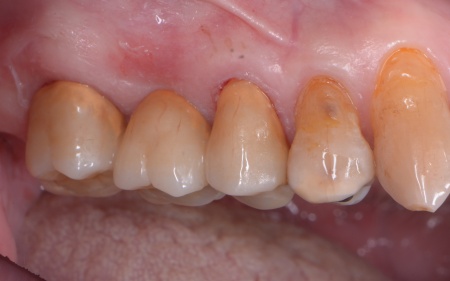

①MTA歯髄温存療法(神経を残す治療) ②根管治療(神経を取る治療) 患者様は「歯を長持ちさせたい」との希望から、①MTA歯髄温存療法を選択されました。 まずブリッジを慎重に取り外し、虫歯を確認します。 数週間後、しみたり痛んだりする症状は認められず、コールドテストとバイタルテストでも歯の神経が問題なく機能している状態であると判断できました。 神経が温存できていることを確認できたため精密な型取りを行い、虫歯の再発リスクが低く強度も高いセラミックのジルコニアでブリッジを新たに作製しました。 |